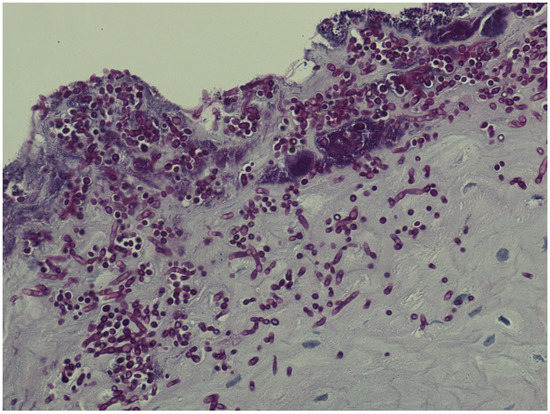

Patients with histologically verified oral Candida hyphae (Figure 1) were significantly older than patients without (p = 0.003), with a medium effect size (Hedges’ g = 0.544). Oral Candida hyphae were more often observed in patients with no alcohol usage (p = 0.012) (Table 5).

Figure 1. Plenty of candida hyphae in oral epithelium.